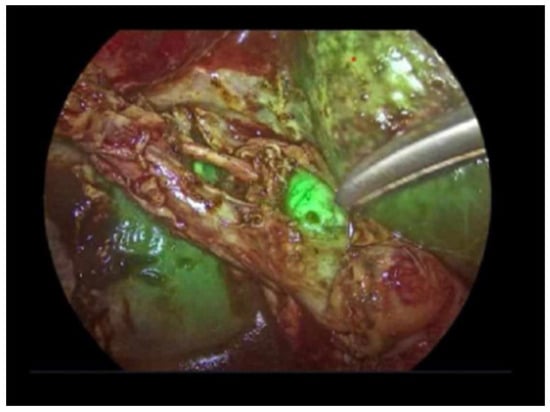

Comparative Evaluation of Standard Cholangiography, Intravenous, and Intracholecystic Indocyanine Green Fluorescence Cholangiography During Elective Laparoscopic Cholecystectomy: Results of a Three-Arm Randomized Trial

Background and Objectives: Bile duct injury is a relatively rare, but critical complication of laparoscopic cholecystectomy and is most commonly attributed to misinterpretation of biliary anatomy. Intraoperative biliary imaging may enhance anatomical recognition and reduce operative uncertainty, yet the optimal imaging modality remains debated. This study aimed to compare conventional intraoperative X-ray cholangiography with two fluorescence-based techniques—intravenous and intracholecystic indocyanine green fluorescence cholangiography—with respect to biliary visualization, perioperative outcomes, and surgeon satisfaction during elective laparoscopic cholecystectomy. Materials and Methods: This prospective, single-center, single-blind randomized controlled trial included 240 adult patients scheduled for elective laparoscopic cholecystectomy between June 2021 and December 2022. Participants were randomized equally to standard intraoperative cholangiography, intravenous indocyanine green fluorescence cholangiography, or intracholecystic indocyanine green fluorescence cholangiography. The primary outcome was successful visualization of predefined extrahepatic biliary landmarks, including the critical junction. Secondary outcomes included cholangiography duration, perioperative complications, postoperative inflammatory markers, and surgeon satisfaction assessed using a five-point Likert scale. This study was registered at ClinicalTrials.gov (NCT04908826). Results: Visualization rates of the critical junction and major extrahepatic bile ducts were comparable among three groups, with no statistically significant differences observed. Both fluorescence-based techniques achieved a 100% technical success rate, whereas standard cholangiography failed in a small proportion of cases. Cholangiography duration was significantly shorter in the fluorescence groups compared with standard cholangiography (p < 0.001). Surgeon satisfaction scores were significantly higher for both fluorescence approaches, with a slight preference for intravenous administration. Perioperative complication rates and postoperative inflammatory markers were com-parable among groups. Conclusions: Intravenous and intracholecystic indocyanine green fluorescence cholangiography are non-inferior to conventional intraoperative cholangiography for biliary anatomy visualization and offer advantages in procedural efficiency and surgeon satisfaction. Fluorescence-based imaging represents a safe and effective alternative for intraoperative biliary mapping during elective laparoscopic cholecystectomy. Full article

Show Figures

Figure 1